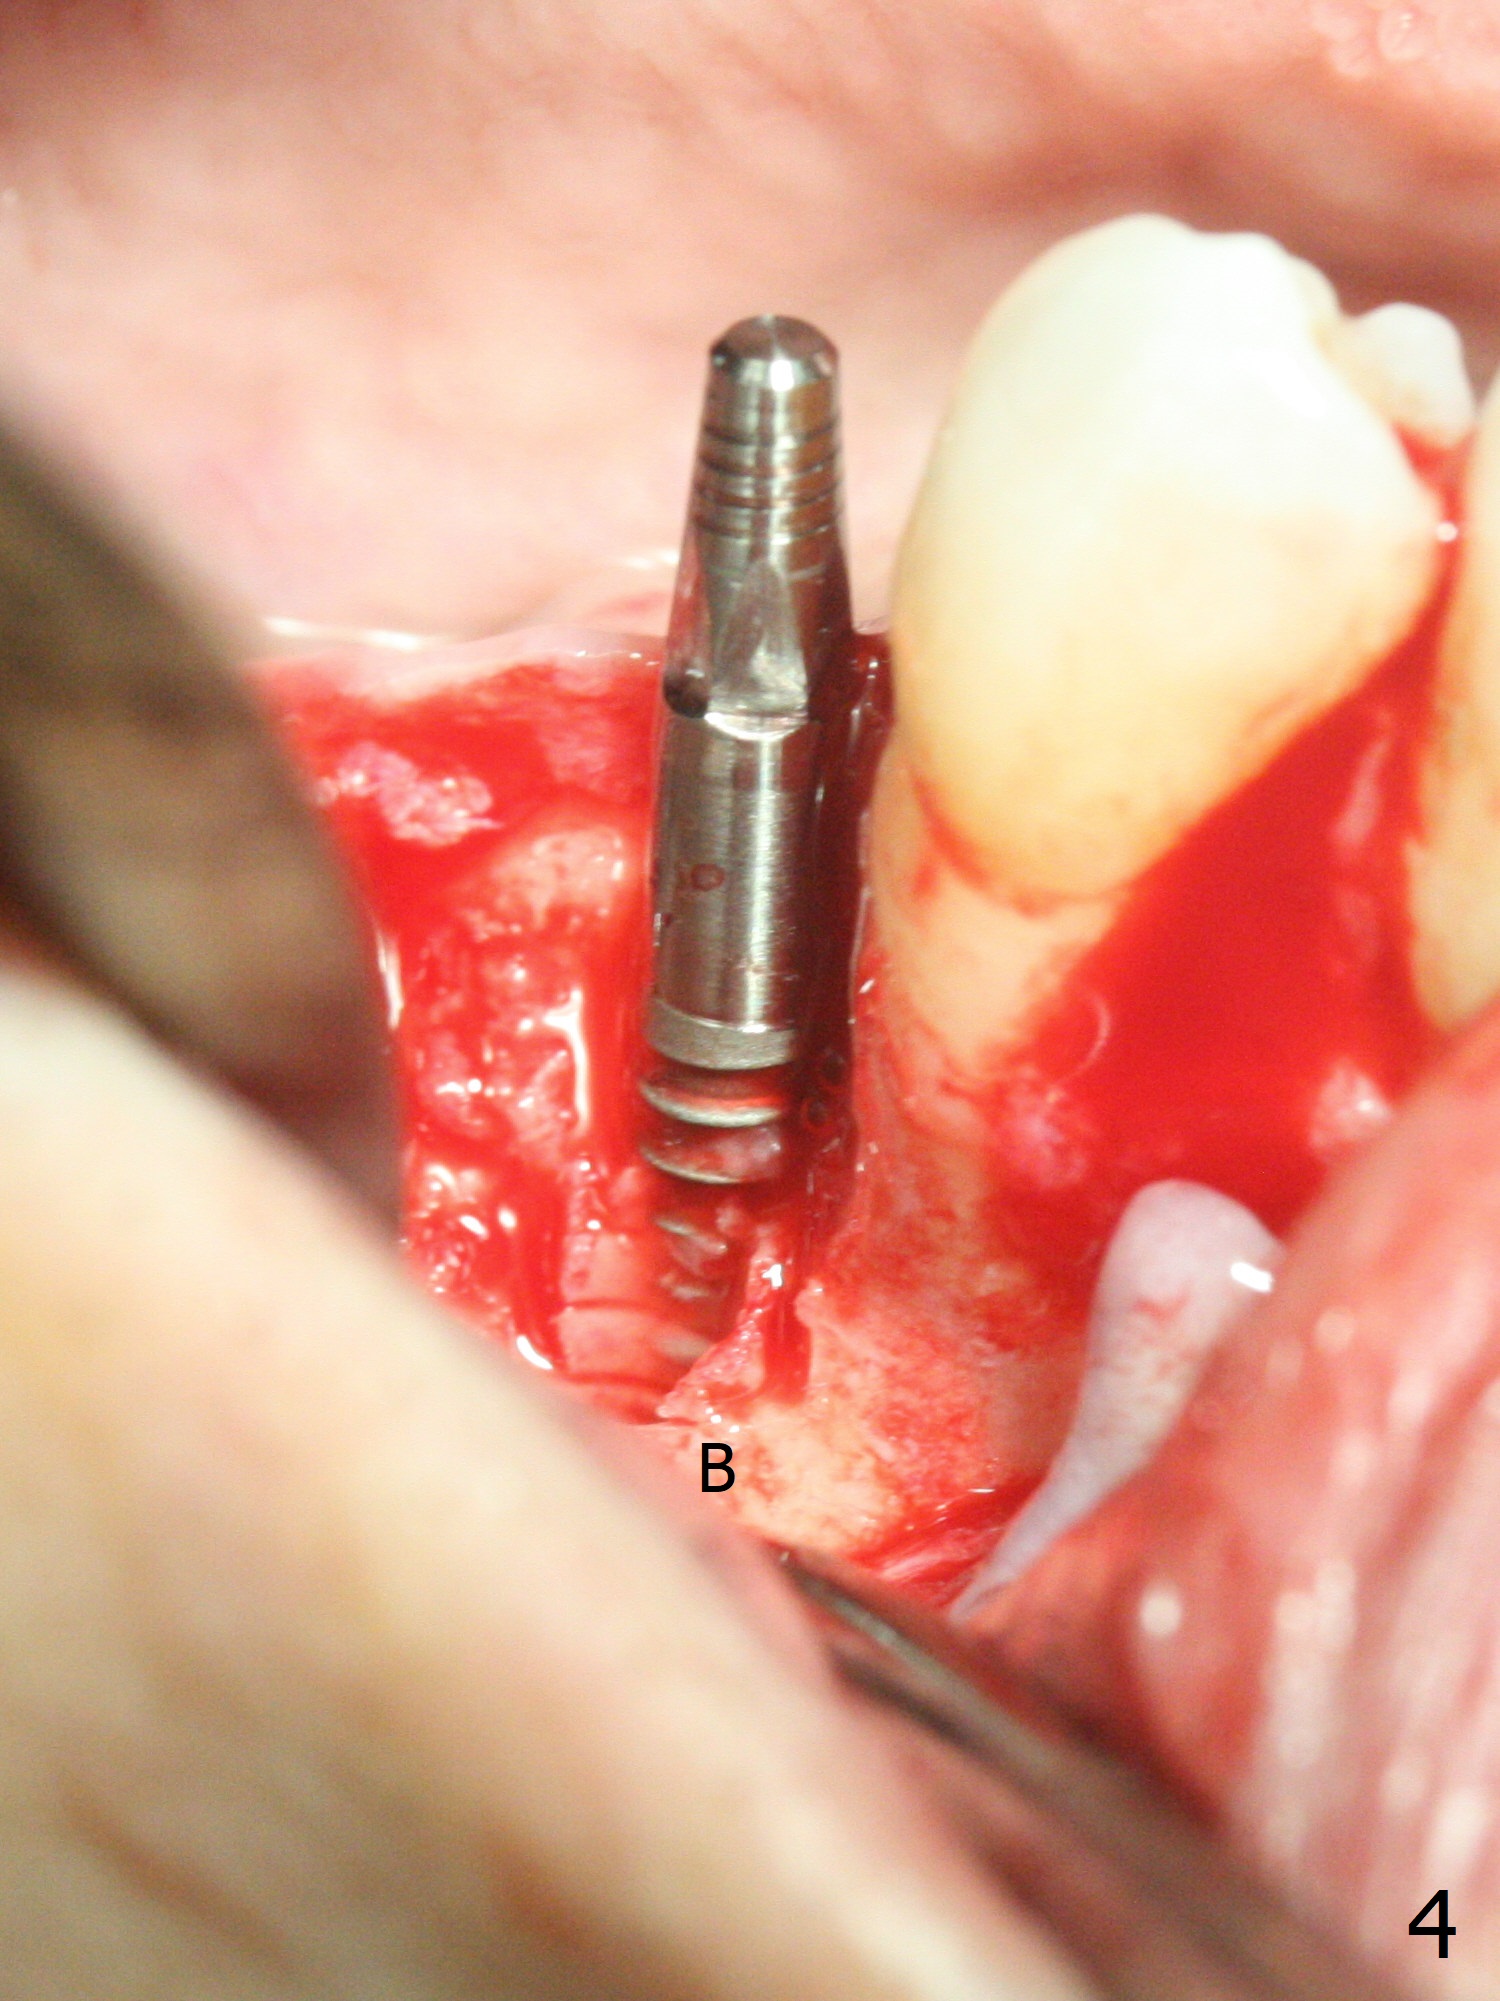

The buccal gingiva is recessive at #29 and 30 (Fig.1). Incision reveals buccal implant thread exposure with circum-ferential granulation tissue (Fig.2 *). Immediate post implant removal at #29, osteotomy is initiated lingual (Fig.3 (intraop CT, coronal section) ). A smaller and shorter implant (3x12 mm vs. 3.5x13 mm) is placed away from buccal (Fig.4 B, 5).